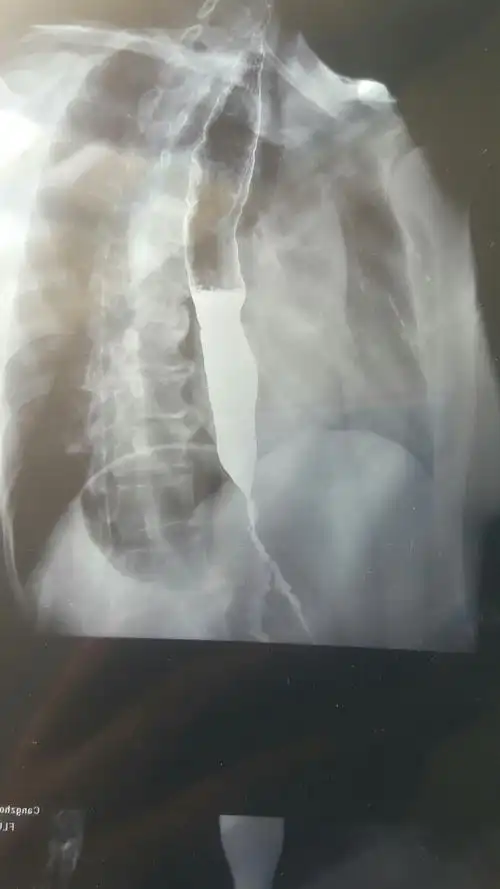

a图为鸟嘴征,b图为乙状结肠样改变

贲门失迟缓症的鸟嘴样改变